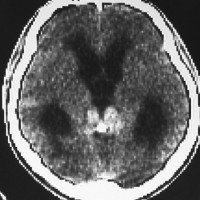

1984年 19歳の時に,松果体のジャーミノーマに全脳照射45グレイで治療されました(左CT)。1997年左蝶形骨縁にヘマンジオペリサイトーマが発生しました(中央と右のMRI)。手術で全摘出しましたが4年後,2001年に脊髄に播種再発してつらい経過を辿りました。眼窩壁を破る典型的なヘマンジオペリサイトーマの像で,放射線誘発髄膜腫との鑑別がとても大切なものです。

左側の画像は照射後再発を手術摘出後です,数ヶ月で再燃しています,かなり早い増殖速度で再発してきて取りきれません